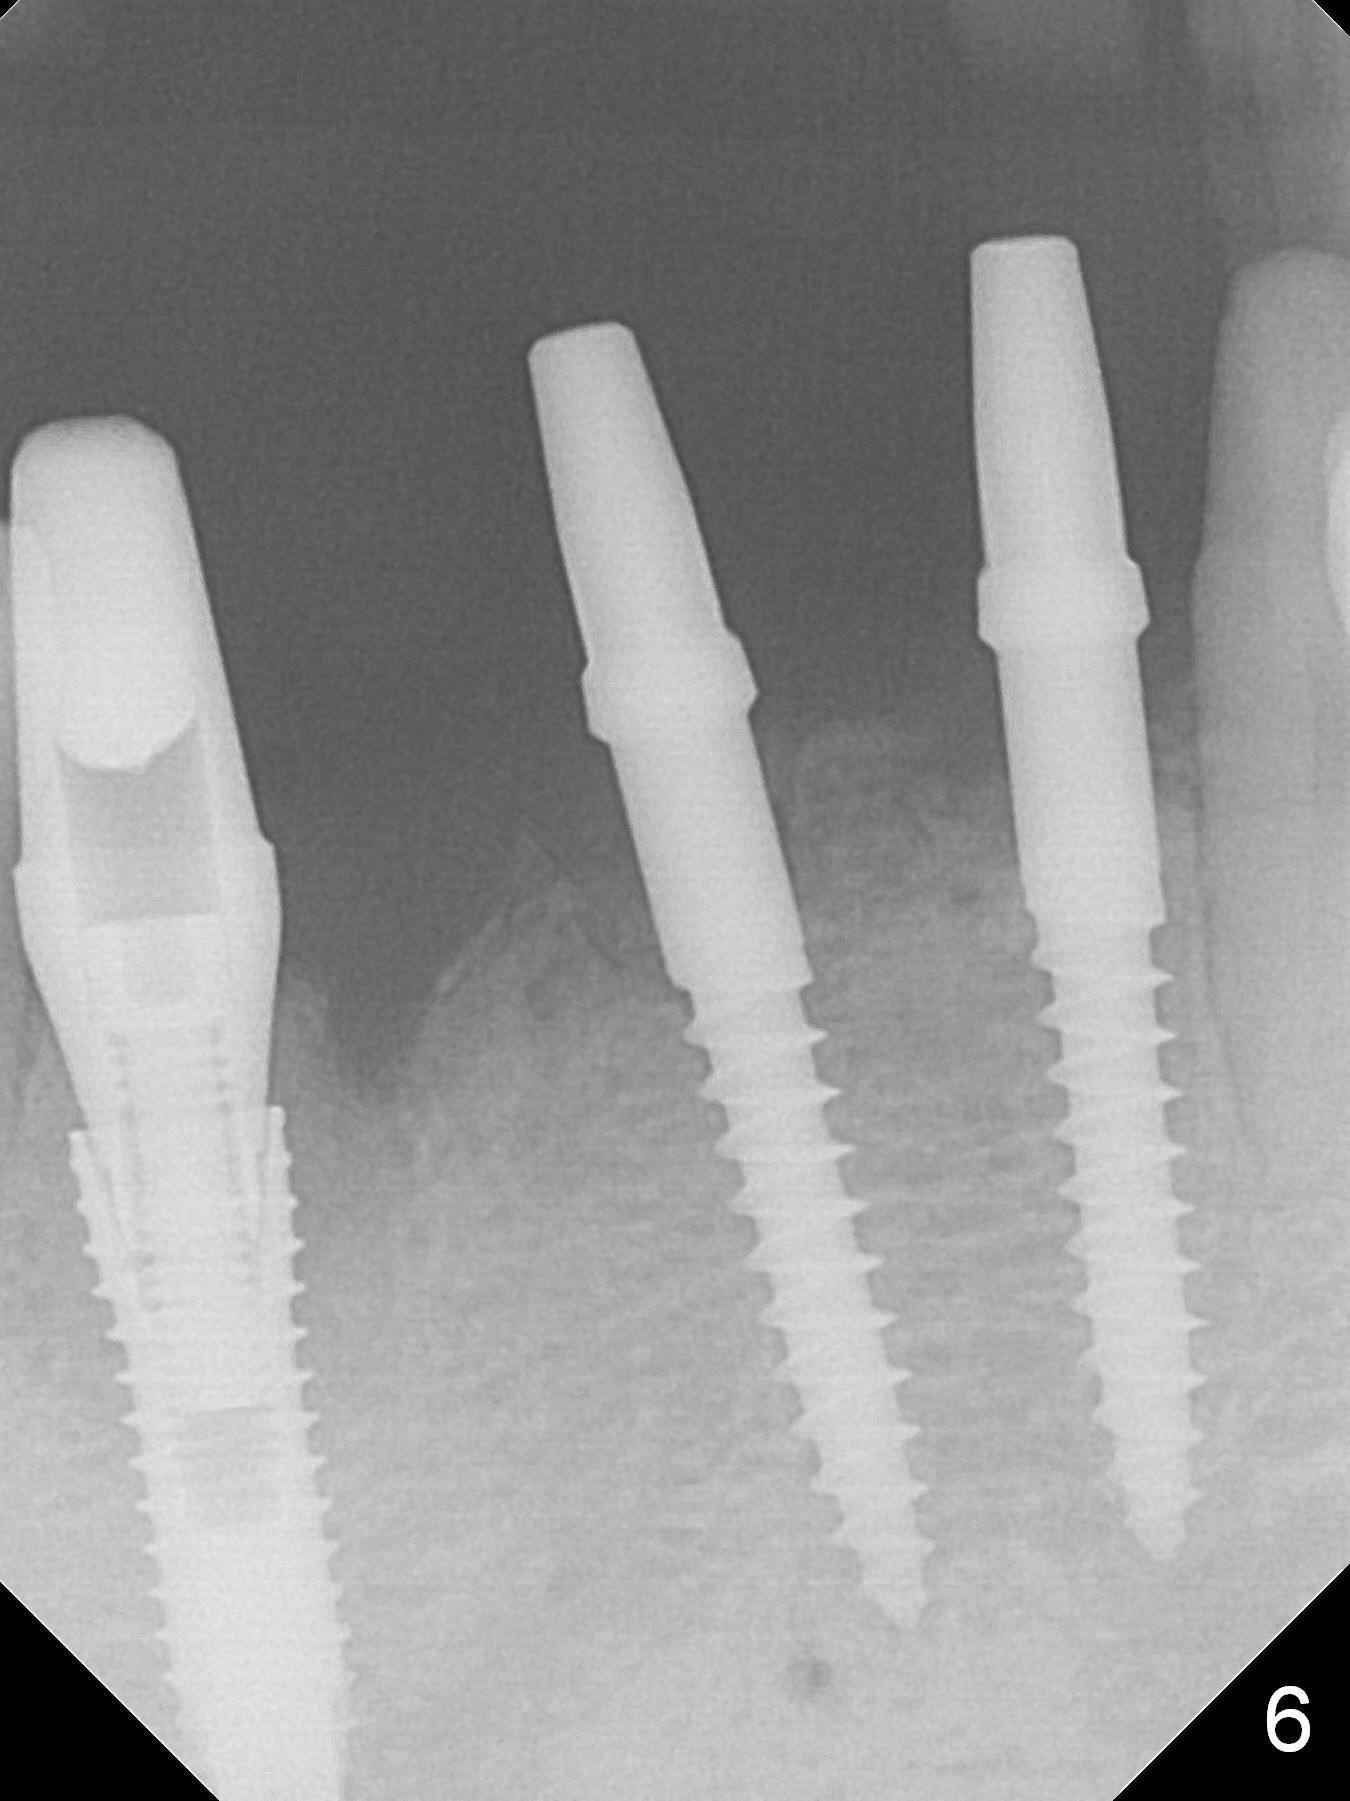

Since the ridge between the lower canines is atrophic (Fig.2), osteotomy starts at #23 and 25 after crestal reduction (Fig.4 arrowheads), Two of 2.5x12(4) mm 1-piece implants are placed (Fig.6). The implants at #23, 25 and 27 and the tooth #22 support an immediate provisional bridge (Fig.7).